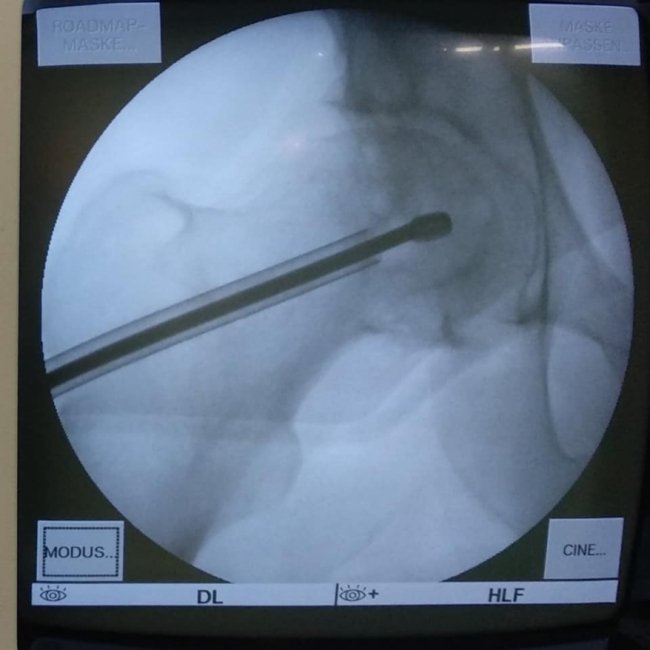

В ході подальшого дослідження в головці правої стегнової кістки виявили кисту розмірами 2*2*2,5 см.

"В ході клінічного розбору було прийняте рішення на користь органозберігаючої операції. Куратор напрямку пухлин та пухлиноподібних захворювань Шевчик Я.В. виконав унікальну операцію: декомпресійну пластику кисти головки стегнової кістки", - йдеться в дописі.

Ця операція полягає у видаленні вмісту кисти, очищенні її стінок та виповнення дефекту кістковим трансплантатом з доступу розміром 3 см.